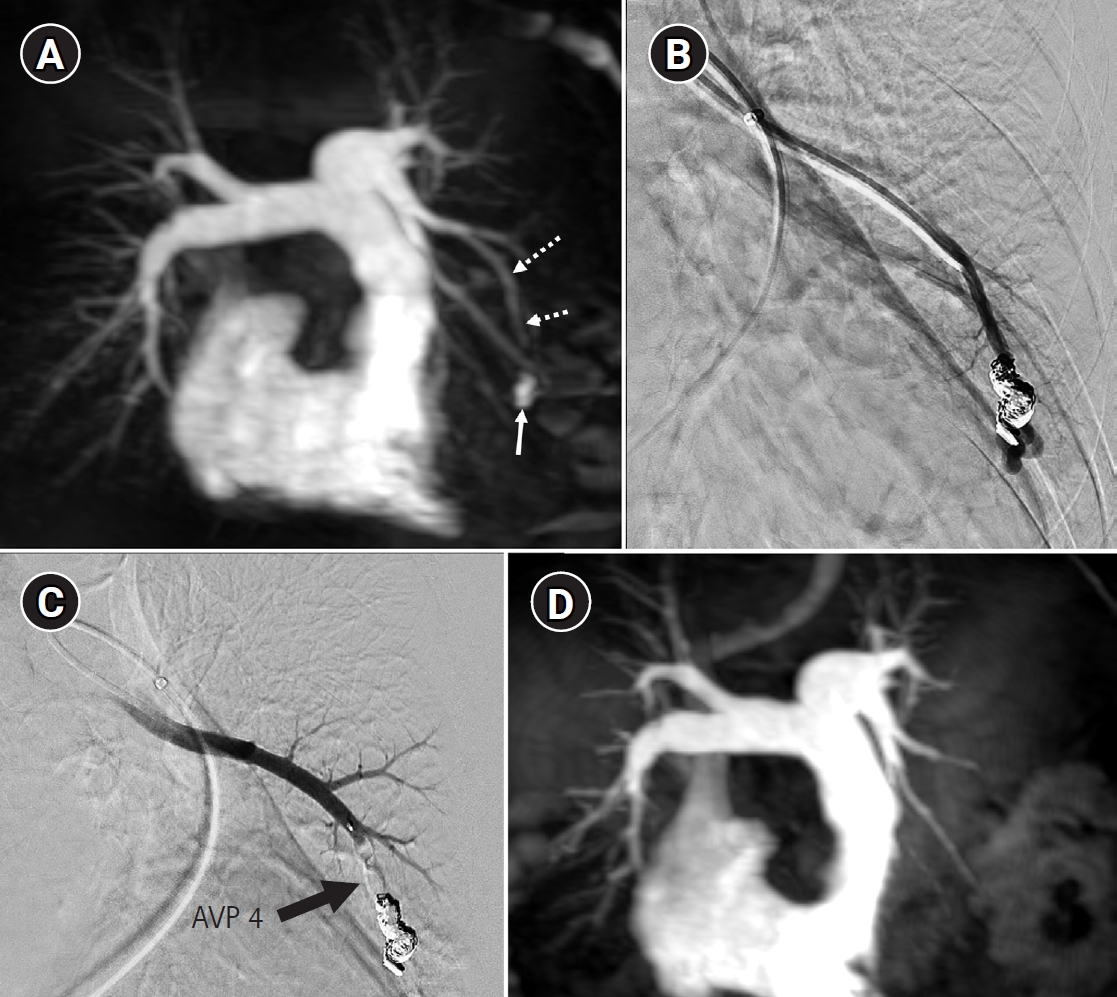

Fig. 6.

Time-resolved magnetic resonance angiography (TR-MRA) and procedural images of a pulmonary arteriovenous malformation showing recanalization. (A) In the TR-MRA performed before the procedure, a venous sac (arrow) is observed concurrently with the feeding artery (dashed arrows). (B) Recanalization was confirmed in the selective angiography. (C) Utilizing additional coils and an 8 mm Amplatzer vascular plug type IV (AVP 4) (arrow), the feeding artery embolization was carried out. (D) On the 6-month follow-up TR-MRA, the feeding artery is no longer visible, and the venous sac is also not observed.

kjir-2026-00010f6.jpg

Long-term follow-up after treating PAVMs is needed to detect newly developed PAVMs and to identify persistence or recurrent flow [10,11]. Treatment failure in PAVMs can be classified as recanalization and reperfusion. Recanalization refers to the reopening of blood flow through spaces between the previously placed embolic material (Fig. 6). Reperfusion, on the other hand, occurs when blood flow from an adjacent pulmonary artery reopens the previously embolized distal vein or venous sac (Fig. 7) [32]. As the primary follow-up modality, CT is recommended, but there are currently no specific guidelines on whether or not to use contrast enhancement [33]. It is recommended to perform an initial evaluation by CT about 6 months after PAVM embolization, and then follow-up with CT every 3–5 years thereafter (Fig. 8). In CT follow-up, the evaluation is based on the reduction rate of the venous sac or the draining vein, and the traditional criterion is that there should be at least a 70% reduction in the size of the venous sac or draining vein [34,35]. In recent studies, there have been opinions that this 70% size reduction criterion is too strict. In response, some research using angiographic-confirmed cases or time-resolved magnetic resonance angiography (TR-MRA) has proposed a 50%–60% guideline [36,37]. When using CT, repeated radiation exposure and metal artifacts from the coils can be problematic. By using metal artifact reduction techniques, it is possible to obtain clear images of the surrounding parenchyma, and this also helps in assessing parameters like the draining vein diameter reduction rate (Fig. 9) [38]. Furthermore, low-dose CT protocols may help reduce cumulative radiation exposure during repeated follow-up imaging.